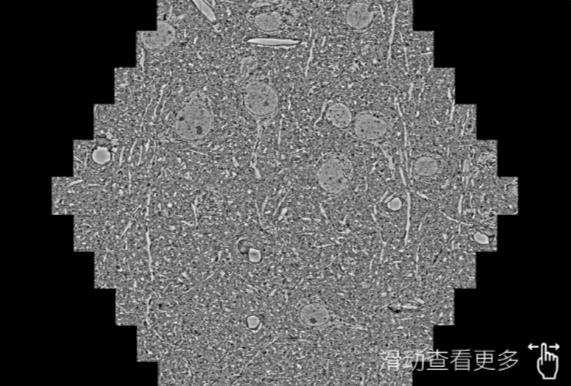

鼠脑切片。左图使用遵义蔡司遵义扫描电镜MultiSEM706对165μmx143pm面积区域成像,耗时仅需1.5秒。右图为鼠脑切片中30μm区域放大效果。样品由芝加哥大学B.Kasthuri提供。

使用蔡司高速遵义扫描电镜MultiSEM对1mm²人脑皮层组织进行高分辨成像,并对其中的各种细胞结构进行三维重构分析。左图展示了2x3mm²组织平面中锥体神经元的三维重构效果。右图显示了局部体积神经元三维重构。图像由哈佛大学chtman实验室提供,渲染图由D. Berger 制作。